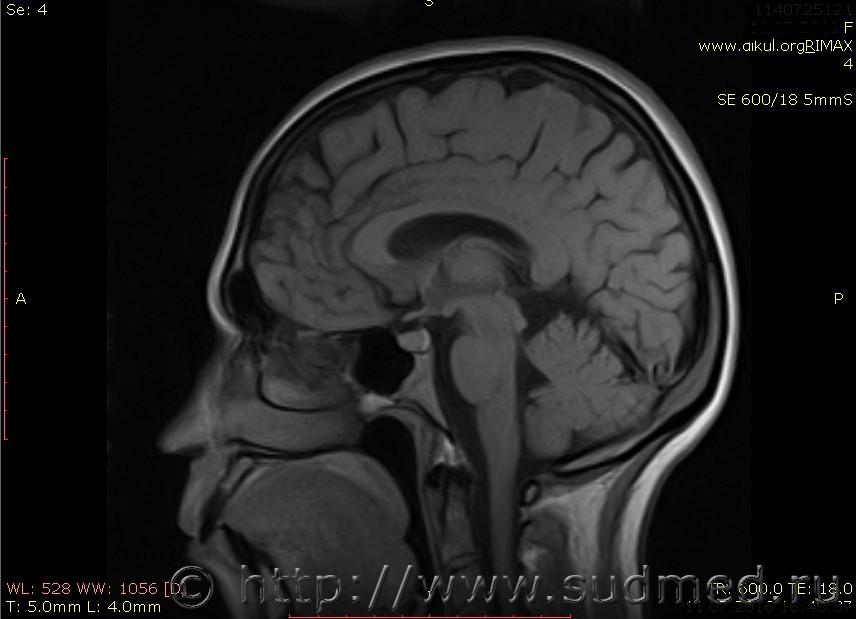

МРТ головного мозга показало: МР-данных за наличие очаговых изменений в веществе головного мозга на момент исследования не выявлено. МР-признаки нарушения соотношения в атланто-осевом суставе. Определяется ассиметрия положения зубовидного отростка С2 относительно боковых масс С1(справа 6,5; слева 4 мм.)

Сама по себе эта информация даёт основания подозревать вывих первого шейного позвонка, но однозначно не свидетельствует о наличии вывиха. Нужно смотреть на снимках наличие реакции со стороны мягких тканей, в т.ч. связочного аппарата, нужно анализировать особенности неврологической патологии, её динамику и проч.

Запрошен электронный вариант снимков из учреждения, где делалось МРТ. Т.к. с самого снимка делать копии не получается,очень мелкие кадры. Завтра попробую вставить в сообщение. (Но СМЭ снимок не смотрел, смотрел только мед.карту, в которой находилось описание МРТ).

Посмотрите пожалуйста снимки, надеюсь на них видны позвонки С1,С2?

Прошу прощения, попробую снова прикрепить файлы. Данные учреждения и пациента убраны.